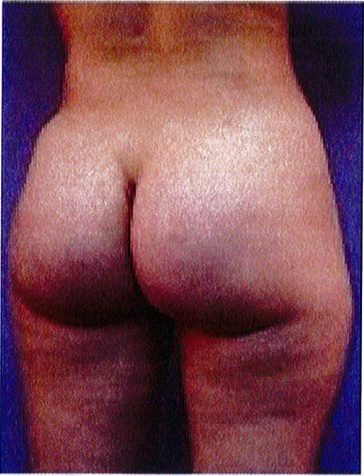

Hình. 18.. (A) Hình anh trước và (B) và sau phẫu thuật làm đầy mông của bệnh nhân được đặt khối implant dưới cân thể tích 225 mL, hai bên.

Bệnh nhân 31 tuổi tiền sử khỏe mạnh, có chỉ định nâng mông bằng implant do thiếu hụt thể tích. Hai khối anatomic implant 225 mL polyurethane dạng gel được đặt ở vị trí dưới cân. Sau phẫu thuật không ghi nhận biến chứng trong suốt quá trình hồi phục, vết mổ liền tốt (Hình 18).